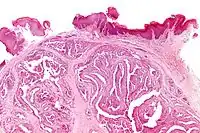

Histopathology

Microscopic histopathological analyses of papillary hidradenoma tumors typically reveal a nodule in the dermis, i.e. layer of skin between the epidermis and subcutaneous tissue. The tumor consists of complex patterns of interconnecting tubular and papillary (i.e. thin finger-like or frond-like) structures.[20] These structures are lined with glandular epithelial and myoepithelial cells. The glandular epithelial cells appear to be excessively proliferating in the ducts leading to the epidermis and show oxyphilic changes, (i.e. cytoplasm filled with large mitochondria, glycogen, and ribosomes) while the myoepithelial cells often appear clear cell-like, i.e. have uncolored cytoplasm when stained with hematoxylin and eosin.[1] The histopathology of anogenital and ectopic papillary hidradenomas are similar to each other.[7][9][15][18]